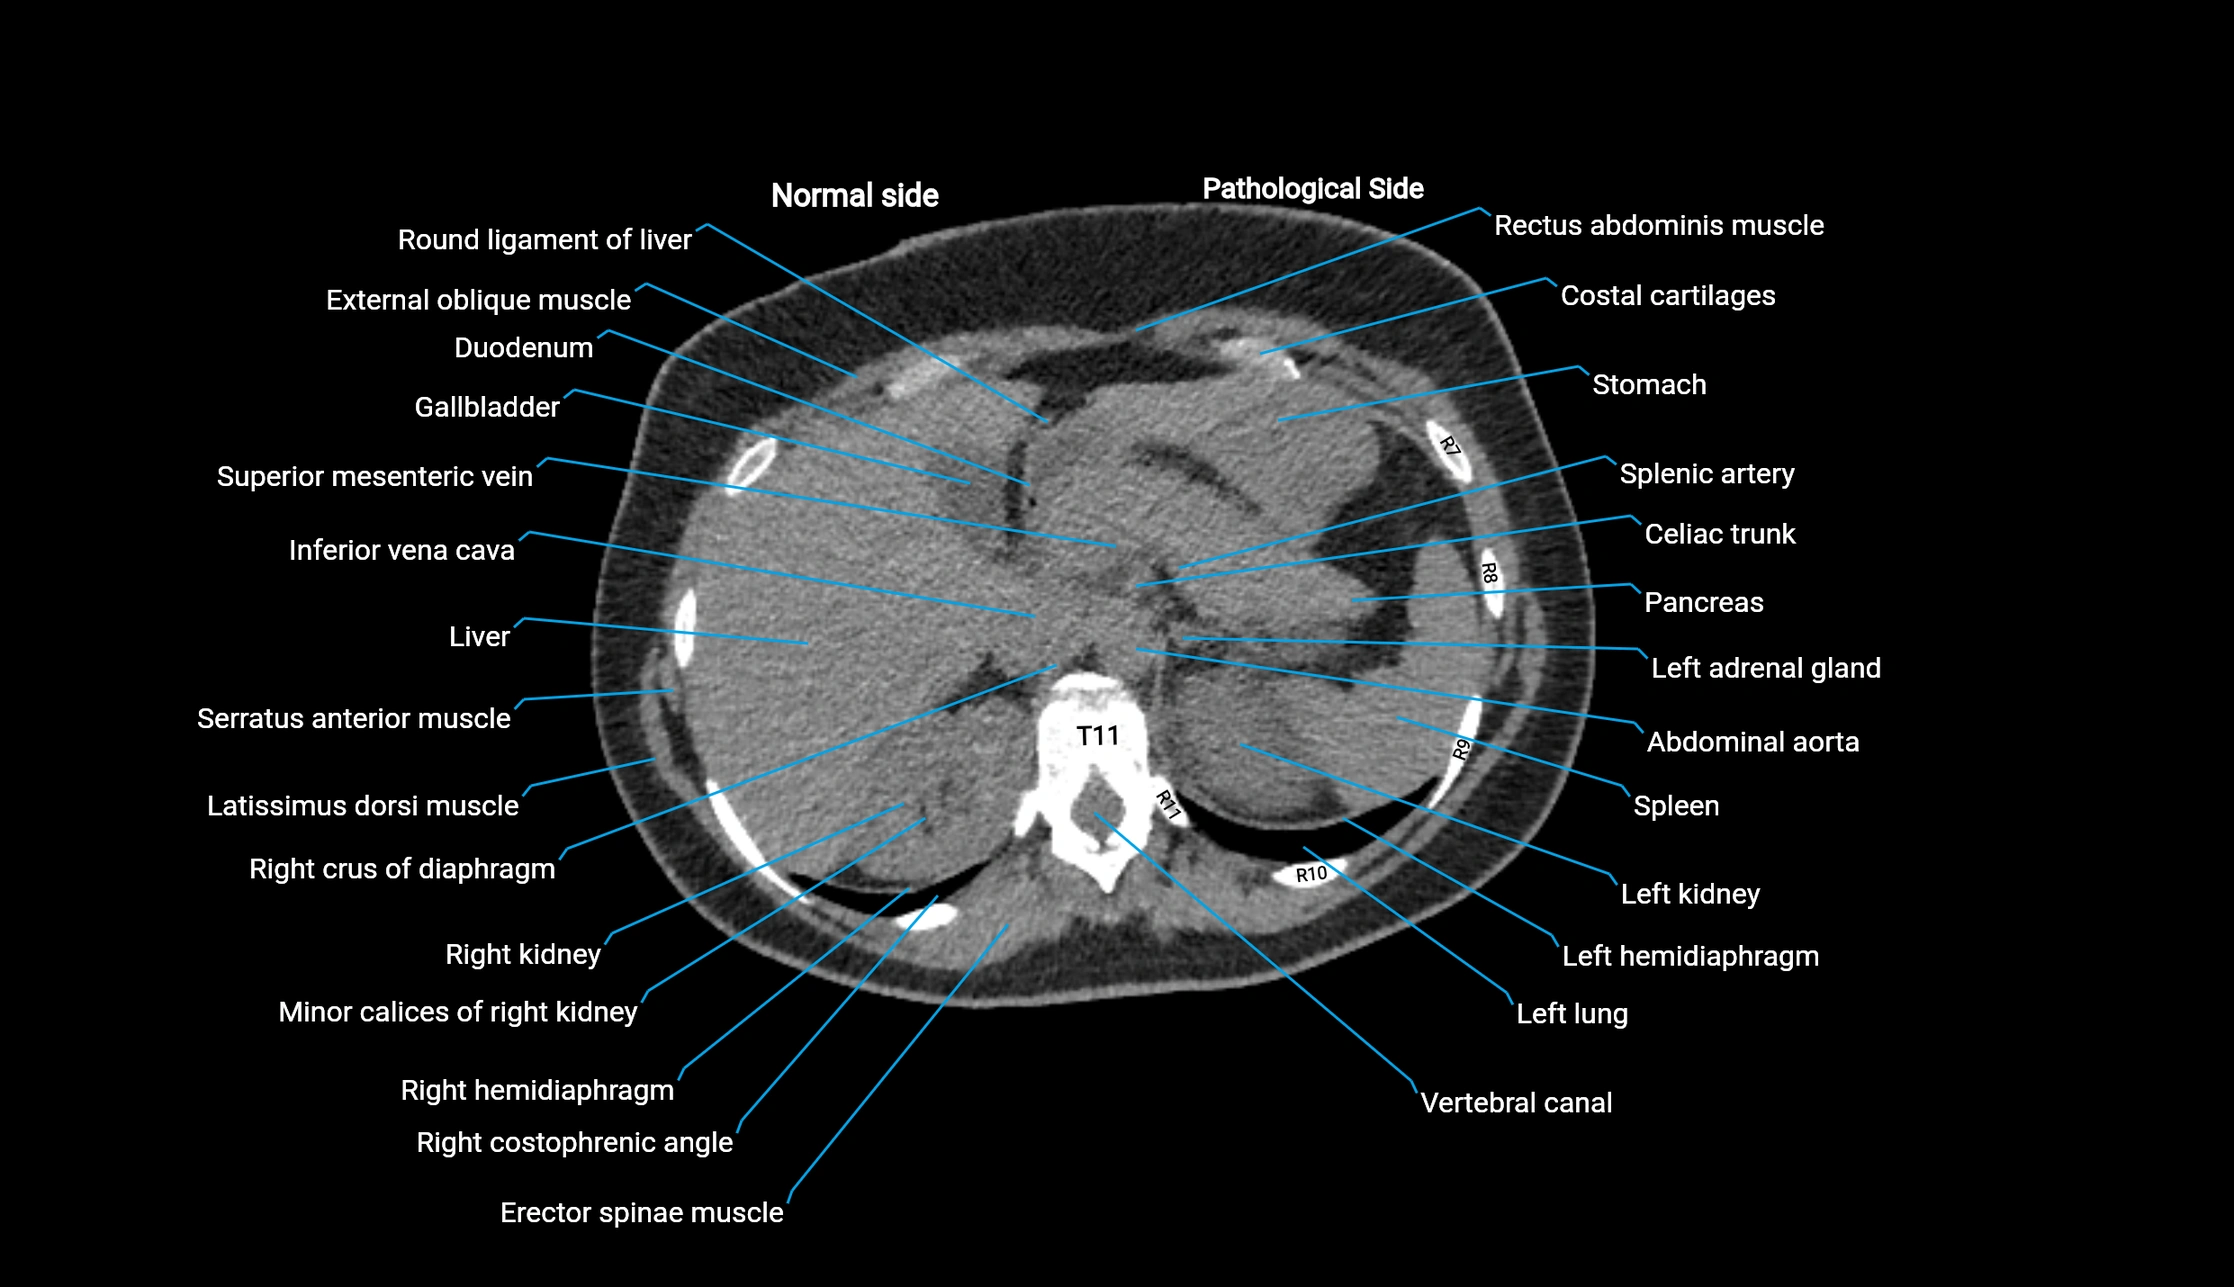

CT image

image